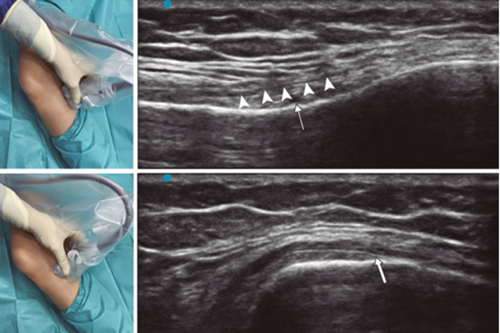

Ultrasound-guided genicular nerve radiofrequency

Fig. 3. Sonoanatomy and technique for performing superior medial genicular nerve block (SMGN). The transducer is located on the distal long axis of the femur and once the position of the SMGN (asterisks) is known, the probe is rotated 90 degrees to obtain a view of the femur short-axis (don't forget to keep the same depth that we find the SMGN on the long axis). VM (vastus medialis).

In order to achieve a correct location of anatomical landmarks by ultrasound we must place the patient in supine position with the knee flexed and a pillow under the popliteal fossa (14,16,19).

Fig. 4. Sonoanatomy and technique for performing inferior medial genicular nerve block (IMGN). The transducer is located on the proximal long axis of the tibia and we identify the vasculonervious package of the IMGN (arrow) just below medial collateral ligament (arrowheads). Then the probe is rotated 90 degrees to obtain a short-axis view of the tibia (don't forget to keep the same depth as the IMGN found on the long axis).

After performing knee asepsis/antisepsis, surgical field placement, and the sterile sheath of the high frequency linear transducer, we proceed to locate the SMGN (Figure 3). Placing the probe in a coronal plane on the inner face of the knee, we slide it cranially to visualize the junction of the metaphysis to the femoral diaphysis and the superior medial genicular artery/nerve (ASMGN), usually located near the periostium of the femur (if this neurovascular structure is not found, the junction between metaphysis and femoral diaphysis is taken as a reference). The mid-point of the transducer corresponding to ASMGN is then marked on the skin and the transducer is rotated to be placed in the transverse or axial plane to view ASMGN on the short axis (if this structure is not visible, confirm that we are at 50 % depth of the femur). In this cross-section the needle of the TRF is advanced in plane from anterior to posterior toward the ASMGN or to a depth of 50 % of the thickness of the femur. Finally, the transducer is rotated 90° again, leaving it in a coronal plane to check that the needle tip is near the ASMGN or the junction of the metaphysis and femoral diaphysis (14,16,19).

To locate the IMGN (Figure 4), we placed the transducer in a coronal plane on the inner face of the knee, sliding it caudally to identify the diaphysis junction with the tibial metaphysis and the inferomedial genicular artery/nerve (AIMGN). And we repeat the same steps we used for SMGN. If the AIMGN is not found, the reference to be taken shall be the depth of 50 % of the thickness of the tibia (14,16,19).

To locate the SLGN, the patient must be supine with the lower limb in internal rotation, obtaining good exposure to the lateral side of the thigh. We place the linear transducer in a coronal plane on the lateral side of the knee, slide it in a cranial direction to visualize the junction of the metaphysis with the femoral diaphysis and the superior lateral genicular artery/nerve (ASLGN), and repeat the same steps that we use for SMGN (14,16,19).